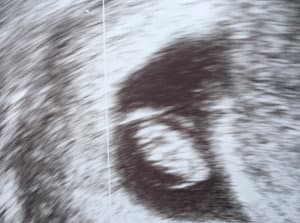

Zum Glück kamen wir recht schnell dran und die Ärztin machte dann auch schon gleich den ersten Ultraschall. Und dort sah man es ganz deutlich: 1,1 cm groß und momentan noch eher ein kleiner Haufen aber das Herz schlug deutlich sichtbar. Das war ein ganz merkwürdiger, bewegender, verrückter Moment. Auf einmal war es ganz real, dass da tatsächlich etwas in meinem Bauch wächst – nicht etwas! Ein Baby!

Die Ärztin gab uns noch einige Hefte zum Thema Schwangerschaft, ein paar Werbe-Flyer und zwei neue Termine mit nach Hause. Dort angekommen, konnte ich gar nicht anders als ständig auf das ausgedruckte Ultraschall-Bild zu gucken. So surreal. So unvorstellbar. Und das aufregendste, wunderbarste, beeindruckendste!